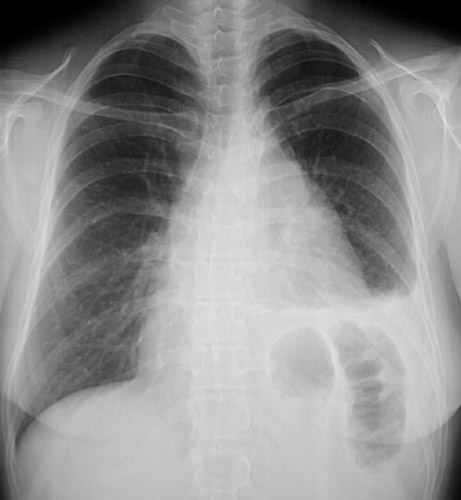

In the PA view of a chest radiograph ahove, there is a large anterior mediastinal mass which proved to be Hodgkin's disease. There is also an elevated left hemidiaphragm from left phrenic nerve invasion by the mass. The lateral view is seen below.